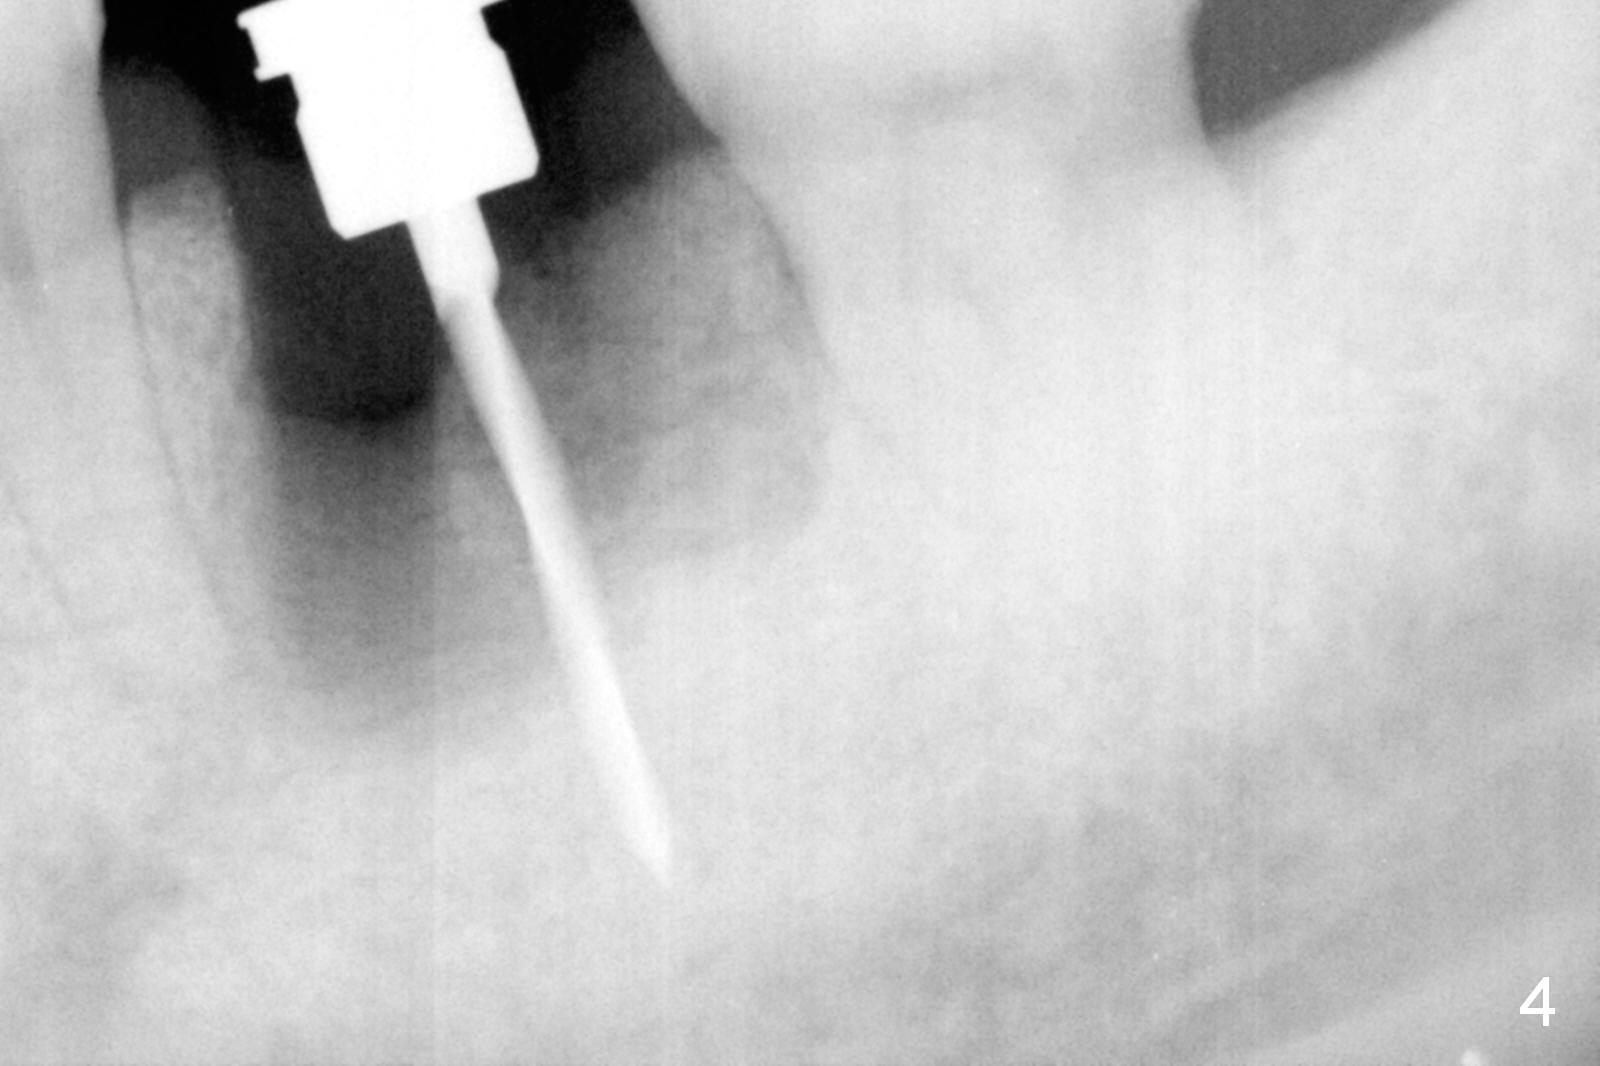

The asymptomatic tooth (#19) has a midbuccal fistula (Fig.1 <). The mesiobuccal pocket is 10 mm with purulent discharge from the sulcus (Fig.2,3). The mesiobuccal wall defect is confirmed when the tooth is extracted. Osteotomy is initiated lingually in the septum following septal crestoplasty (flattening) (Fig.4: using 1.6 mm drill for 9 mm). Since the lingual portion of the osteotomy is higher, it is difficult to use drill with stopper. For the narrow septum osteotomy, multiple drills are used sequentially (Fig.5 after 4.3 mm drill). A 4.5x11 mm dummy implant is placed (Fig.6) apparently too deep. When a 5x11 mm IBS implant is being placed, the depth is tightly controlled (Fig.7). The implant is apical to the lingual crest, whereas there is ~ 2 mm implant exposure buccally. That is, there is a large gap mesiobuccally (Fig.8), which is filled with .5-1.5 mm allograft (Fig.9 *). A 6.5x5.7(3) mm abutment (A) is placed and trimmed for an immediate provisional (Fig.10 P). The lacerated buccal gingiva is sutured as well as application of Perio Glue.